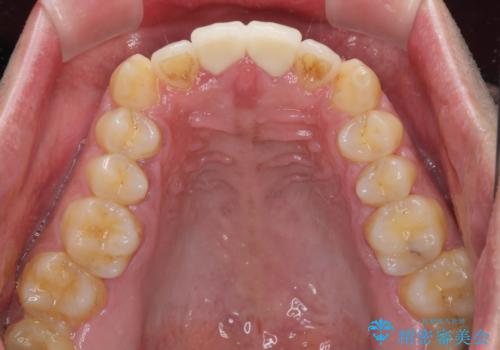

捻れた出っ歯の前歯 オールセラミッククラウンによる審美治療

- 前歯が捻れており出っ歯であることを気にして来院された患者様です。

虫歯がほとんどなく、前歯以外にも歯列に問題があったため、歯列矯正を第一選択として強く勧めました。

しかし、時間をかけることは避けたいという強い要望があったため、セラミッククラウンによる補綴治療を行うこととしました。

補綴治療に先立ち、歯の形態を修正する必要があったため、残念ではありますが根管治療を行うこととしました。